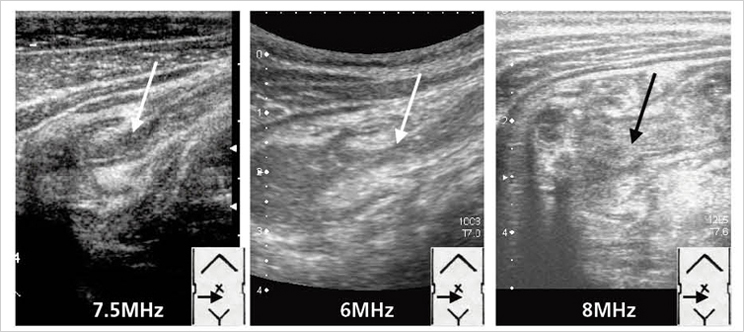

浅井塾直伝!できる小児腹部エコー〜描出・診断・治療まで「いい

小児消化管超音波診断アトラス

診断と治療社

玉井浩

2005/04/01

4787811975

9784787811974